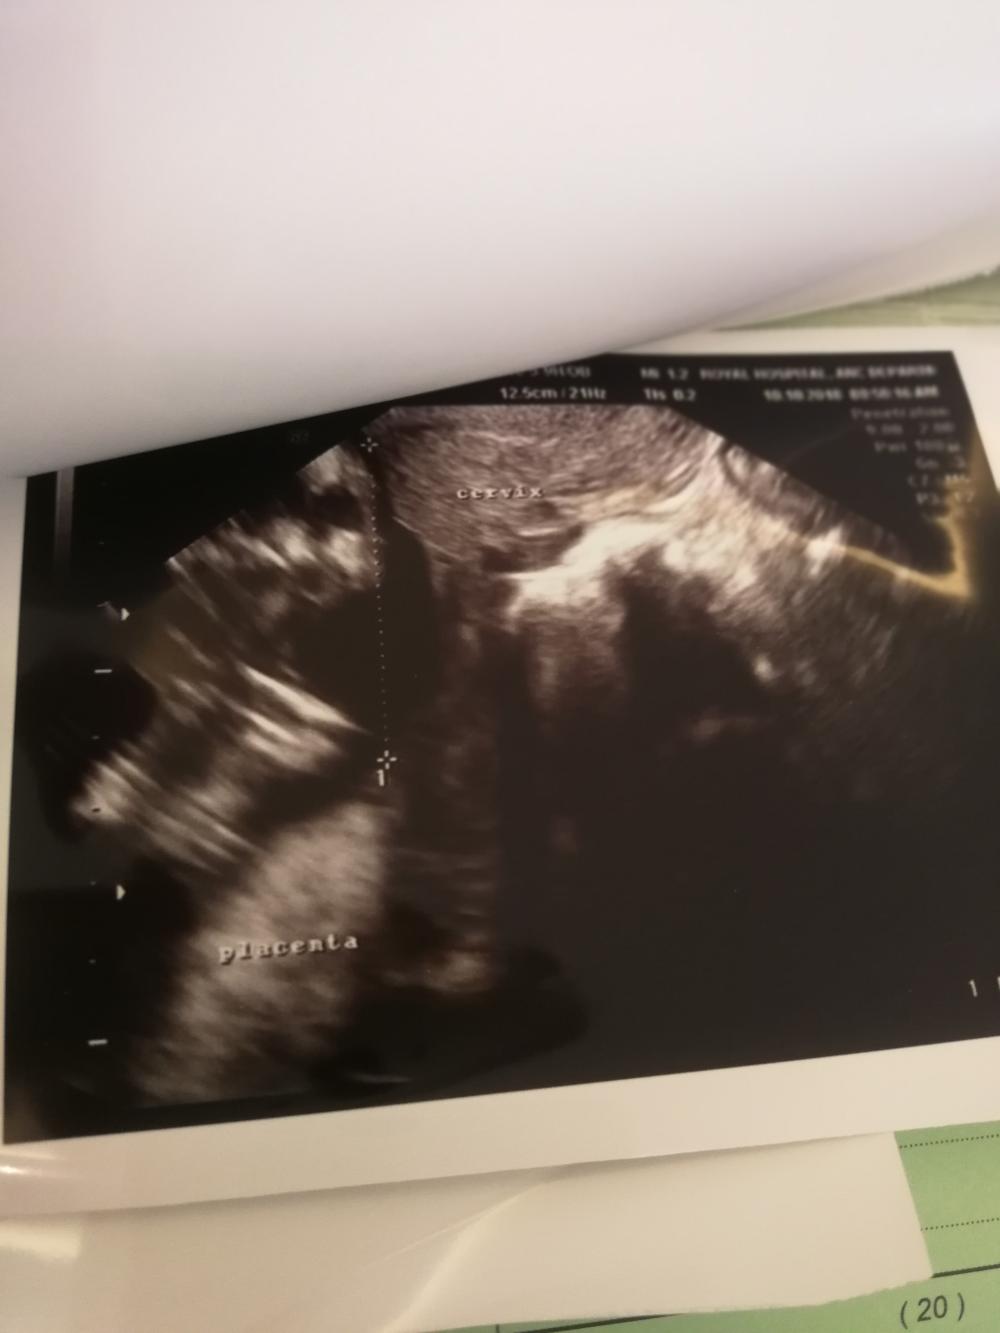

اظن الصور كلهم للمشيمه تو بنزلهن

هذولا